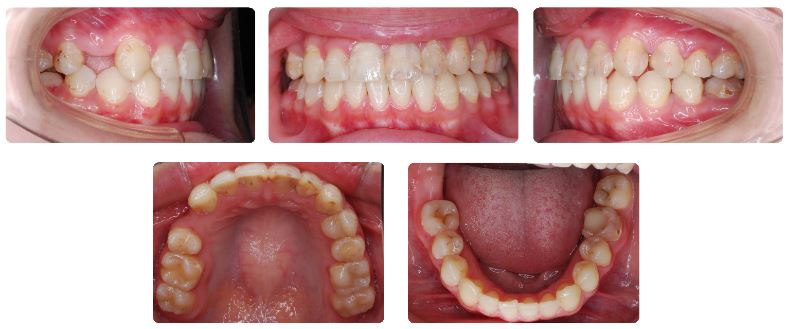

臼歯の早期喪失を伴う過蓋咬合  10代後半

初診時年齢:17歳

性別:女性

診断名:下顎偏位を伴う過蓋咬合

抜歯/非抜歯:非抜歯

装置名:マルチブラケット装置

多数の臼歯が早期に喪失した影響で上下あご全体の噛み合わせが深く真ん中のずれも大きめです。

この咬合状態で今後放置した場合には臼歯の咬合が崩れてしまうことが考えられます。